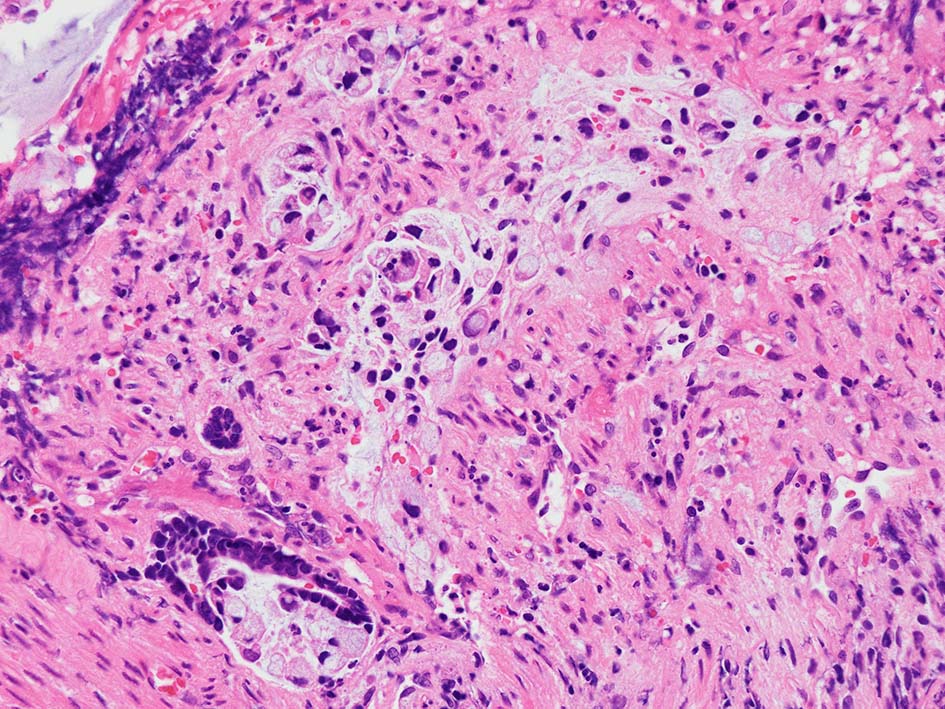

desmoplastic fibrosis, 粘液浸潤のみられる組織片にはsig, porのadenocarcinoma浸潤が確認される.